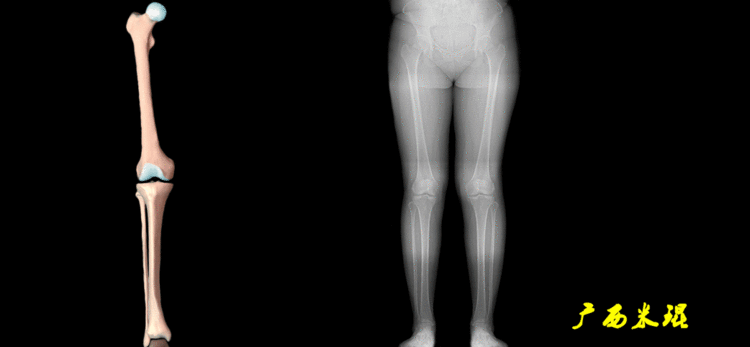

下肢力线及相关角度测量的前提是必须拍摄标准的站立位也就是负重位的下肢全长片。目前这样的照片都是放射科的技师在电脑上拼接出来的,大部分医院的DR都能够做到这一点。

患者直立于摄影架上,后背贴近摄影架,双手自然下垂,膝关节尽量伸直,足部与双肩同宽,要求投照时双髌骨朝正前方,通常患者双足尖应平行向前即可。

提醒一下大家,拍摄过程中应避免下肢的外旋和内旋。如果有一侧肢体短缩时,投照应当用脚垫垫高短缩肢体,使骨盆保持水平,这样下肢短缩测量才精确。如果有肢体旋转畸形时,还是以髌骨朝前为标准,虽然此时双足可能不能保持平行。

无论如何,拍摄出来的下肢全长片必须包含髋关节中心、膝关节中心及踝关节中心,否则对临床是无用的。有了一张下肢的全长照片,我们需要确定下肢关节的中心点,通过中心点画出下肢的各种轴线,然后利用轴线与关节线的相交得出各种所需要的角度。